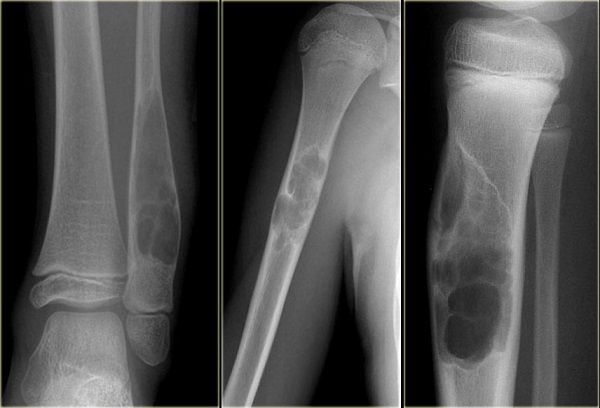

Trong trường hợp không nhận ra nguyên nhân thực sự gây ra các triệu chứng, bác sĩ có thể tiến hành chụp X-quang hoặc các xét nghiệm máu. Xét nghiệm máu cho biết bạn có khỏe hay không, trong khi X-quang giúp bác sĩ tìm ra những đặc trưng bất thường của ung thư.

Khi chụp X-quang, nếu bác sĩ thấy dấu hiệu khối u, bạn sẽ được yêu cầu đến trung tâm y tế lớn để điều trị ung thư xương. Ở đó, bạn sẽ được chụp cộng hưởng từ (MRI) khu vực có khối u để xác định ảnh hưởng của khối u tới dây thần kinh, mạch máu và các khớp gần đó.